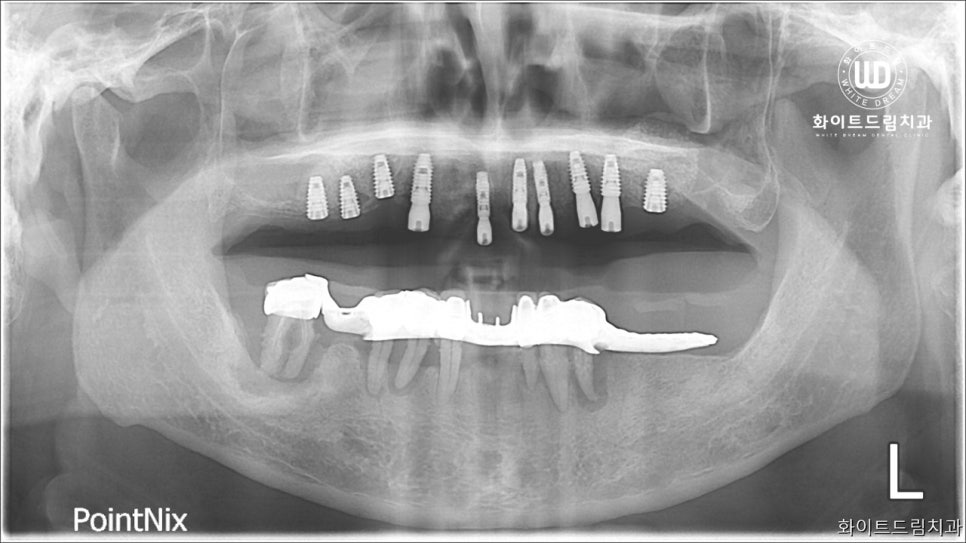

단순 보철 식립이 아닌 기존에 남아있던 치아들이 자라난 방향과 저작상태를 감안하여 임플란트 나사를 식립했습니다. 전체임플란트 사례이나, 고령의 나이이신 점을 감안하여 전반적인 건강상태에 무리가 가지 않도록 상악부터 소량의 임플란트보철을 먼저 식립했습니다.

진행한 치료 기간은 약 6개월 정도 소요되었는데요.

전체 치아를 발치하여 임플란트를 진행하는 것에 대해 걱정이 많으신 환자분이었던 만큼 임플란트 식립 과정에서 지지기능을 튼튼하게 해드리기 위해 치조골 이식술을 동반해드렸습니다.

2주 간격으로 3번에 걸쳐 상악동 거상술과 치조골이식술을 진행하여 뼈가 퇴축하는 것을 방지하고, 심미적으로도 악안면 구조를 재편할 수 있도록 도와드렸습니다. 그리고 5개월 후 임플란트 보철을 올려 마무리 진행을 도와드렸습니다.